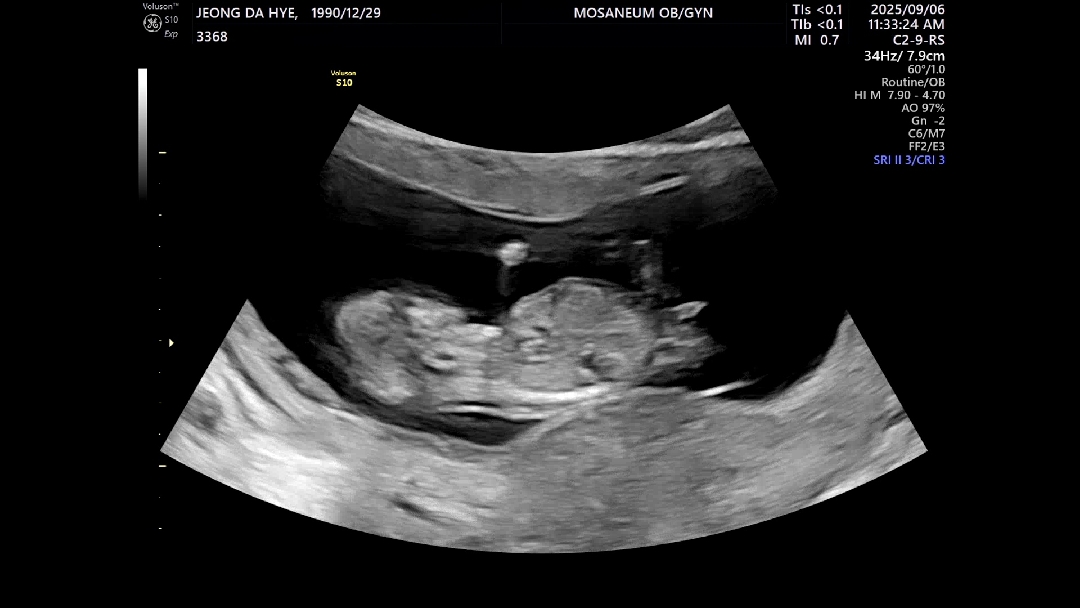

12주 각도법 참견부탁드랴요

12주 초음파인데 의사선생님이 탯줄로 다리감고 있어서 성별 확인 어렵다고 하시긴했는데 동영상 돌려보니 혹시 저 튀어나와있는게 생식기인가 싶어서요... 저게 생식기라면 딸? 아들? 뭐일까욤.... AI는 딸이라고하긴하네욤 ㅋㅋ